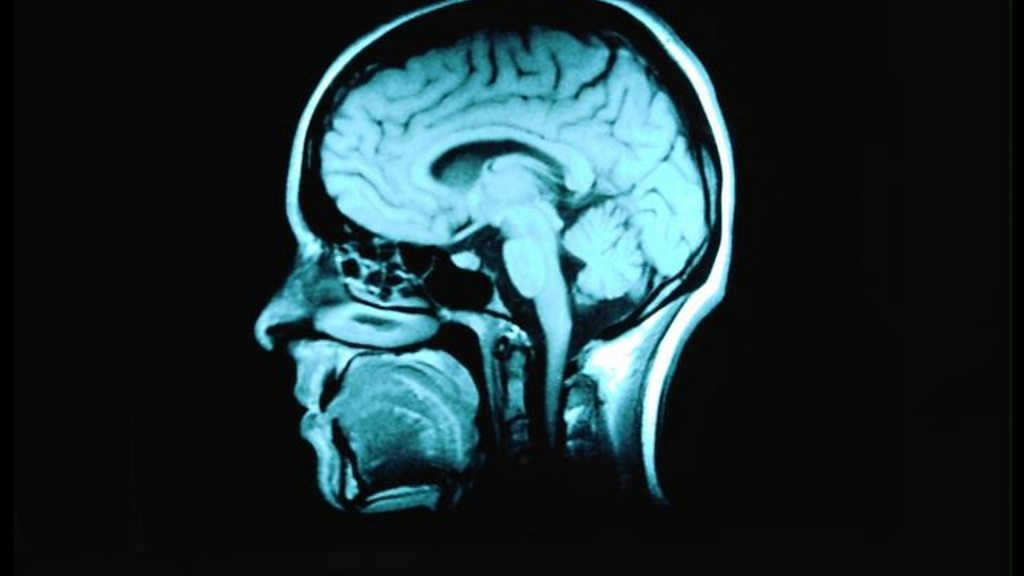

Carly Hopkin from Wool on the invaluable support she got from Gully's Place when her daughter fell ill with a brain tumour

Charlotte Foot meets a mum who was helped through her daughter's terminal cancer journey.